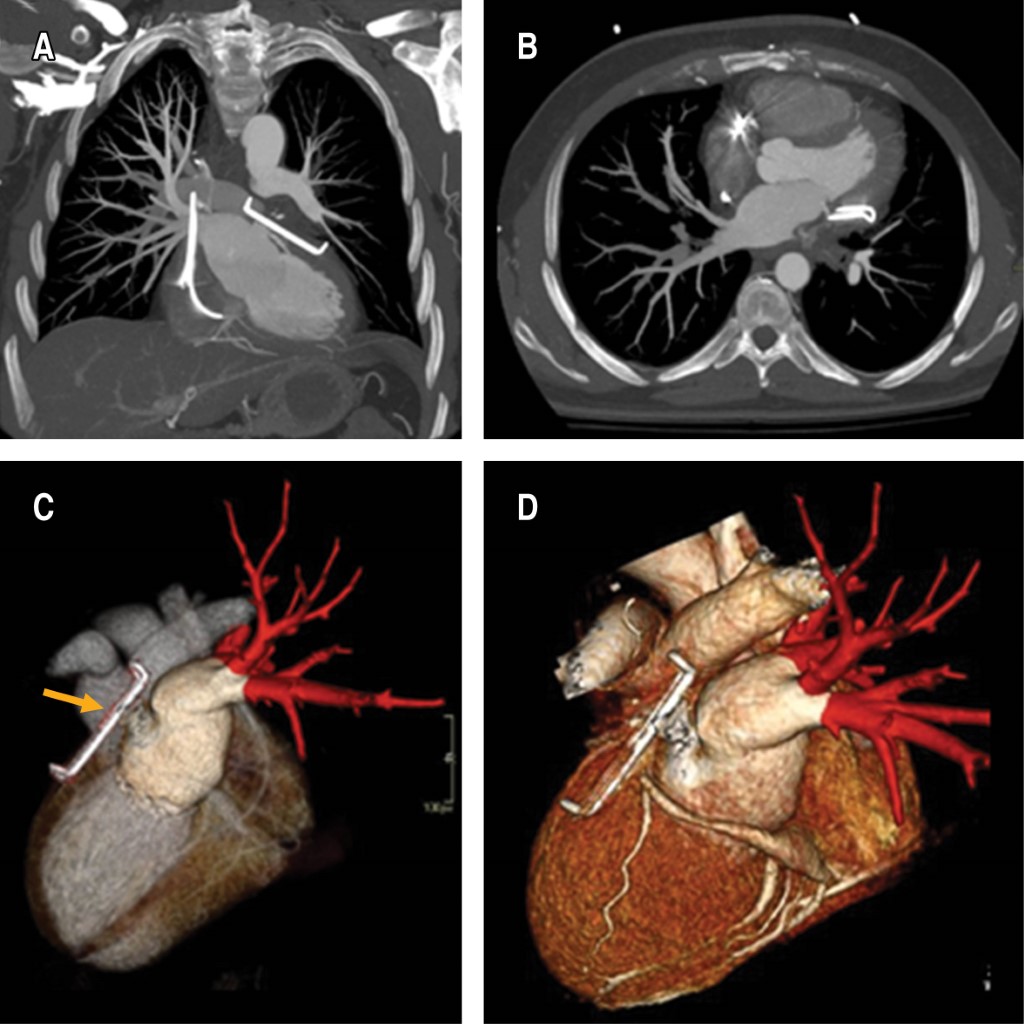

Hemoptisis grave como forma de debut de una estenosis de venas pulmonares izquierdas

La fibrilación auricular es la arritmia más común. Es una patología que conlleva un alto coste sanitario y perjudica la calidad de vida de los pacientes. La ablación percutánea de las venas pulmonares es una terapia consolidada para su tratamiento y varios estudios han demostrado que la recidiva a largo plazo y la mortalidad es menor en comparación con pacientes tratados con medicación antiarrítmica. Presentamos el caso de un varón de 48 años, no fumador, con antecedente de taquicardia auricular incesante de difícil control que acude a urgencias por hemoptisis. El cuadro clínico se debió a una oclusión completa del segmento distal de las venas pulmonares izquierdas como complicación de una ablación percutánea previa. La estenosis de la vena pulmonar es una complicación poco común de la ablación para tratar la fibrilación auricular, siendo un diagnóstico precoz fundamental para mejorar el pronóstico.

Figura 1